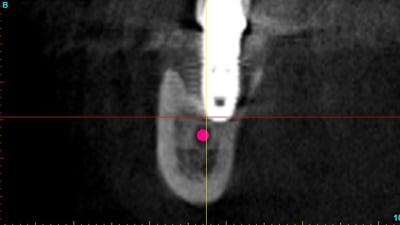

un an après !

ça s'arrange pas, voyez plutôt..

augmentation de la perte osseuse +++

R8 yrwt4t - Eugenol

Sans titre zpbmhm - Eugenol